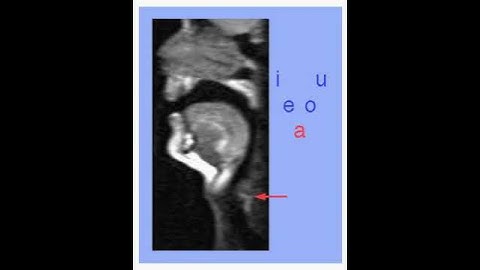

A Simplified Model for the Vocal Tract of [s] with Inclined Incisors - (3 minutes introduction)...